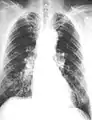

The abnormal chest x-ray and its interpretation remain the most important factors in establishing the presence of pulmonary fibrosis.[11] The findings usually appear as small, irregular parenchymal opacities, primarily in the lung bases. Using the ILO Classification system, "s", "t", and/or "u" opacities predominate. CT or high-resolution CT (HRCT) are more sensitive than plain radiography at detecting pulmonary fibrosis (as well as any underlying pleural changes). More than 50% of people affected with asbestosis develop plaques in the parietal pleura, the space between the chest wall and lungs. Once apparent, the radiographic findings in asbestosis may slowly progress or remain static, even in the absence of further asbestos exposure.[25] Rapid progression suggests an alternative diagnosis.

Extensive fibrosis of pleura and lung parenchyma

61-year-old working industrially with asbestos for decades